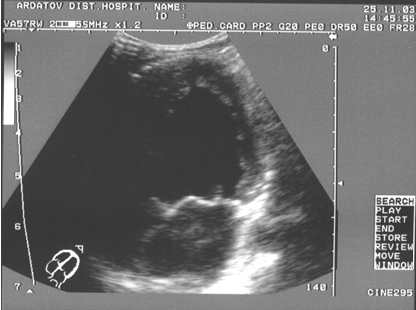

Аневризма межпредсердной перегородки обычно располагается в области овального окна и связана с несостоятельность соединительнотканных элементов. Она возникает при наследственных дисплазиях соединительной ткани, после спонтанного закрытия дефекта межпредсердной перегородки или является врожденной аномалией развития. Обычно аневризматическое выпячивание небольшое, не сопровождается гемодинамическими нарушениями и не требует хирургического вмешательства. Клинически аневризма может быть заподозрена по наличию щелчков в сердце, аналогичных таковым при пролапсе митрального клапана. Возможно также сочетание аневризмы и пролапса. Уточнить характер звуковых изменений в сердце позволяет эхокардиография. Аневризма подтверждается по наличию выпячивания межпредсердной перегородки в сторону правого предсердия в области овального окна (рис. 11). Дети с аневризмой межпредсердной перегородки предрасположены к развитию наджелудочковых тахиаритмий, синдрома слабости синусового узла (D'Urbano M. с соавт.,1994).

Рис.11. Аневризма межпредсердной перегородки, апикальная четырехкамерная позиция (собственное наблюдение).